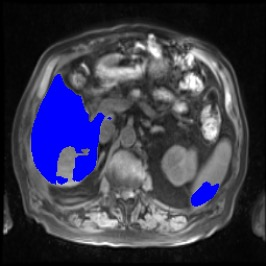

Integrating high-level semantically correlated contents and low-level anatomical features is of central importance in medical image segmentation. Towards this end, recent deep learning-based medical segmentation methods have shown great promise in better modeling such information. However, convolution operators for medical segmentation typically operate on regular grids, which inherently blur the high-frequency regions, i.e., boundary regions. In this work, we propose MORSE, a generic implicit neural rendering framework designed at an anatomical level to assist learning in medical image segmentation. Our method is motivated by the fact that implicit neural representation has been shown to be more effective in fitting complex signals and solving computer graphics problems than discrete grid-based representation. The core of our approach is to formulate medical image segmentation as a rendering problem in an end-to-end manner. Specifically, we continuously align the coarse segmentation prediction with the ambiguous coordinate-based point representations and aggregate these features to adaptively refine the boundary region. To parallelly optimize multi-scale pixel-level features, we leverage the idea from Mixture-of-Expert (MoE) to design and train our MORSE with a stochastic gating mechanism. Our experiments demonstrate that MORSE can work well with different medical segmentation backbones, consistently achieving competitive performance improvements in both 2D and 3D supervised medical segmentation methods. We also theoretically analyze the superiority of MORSE.